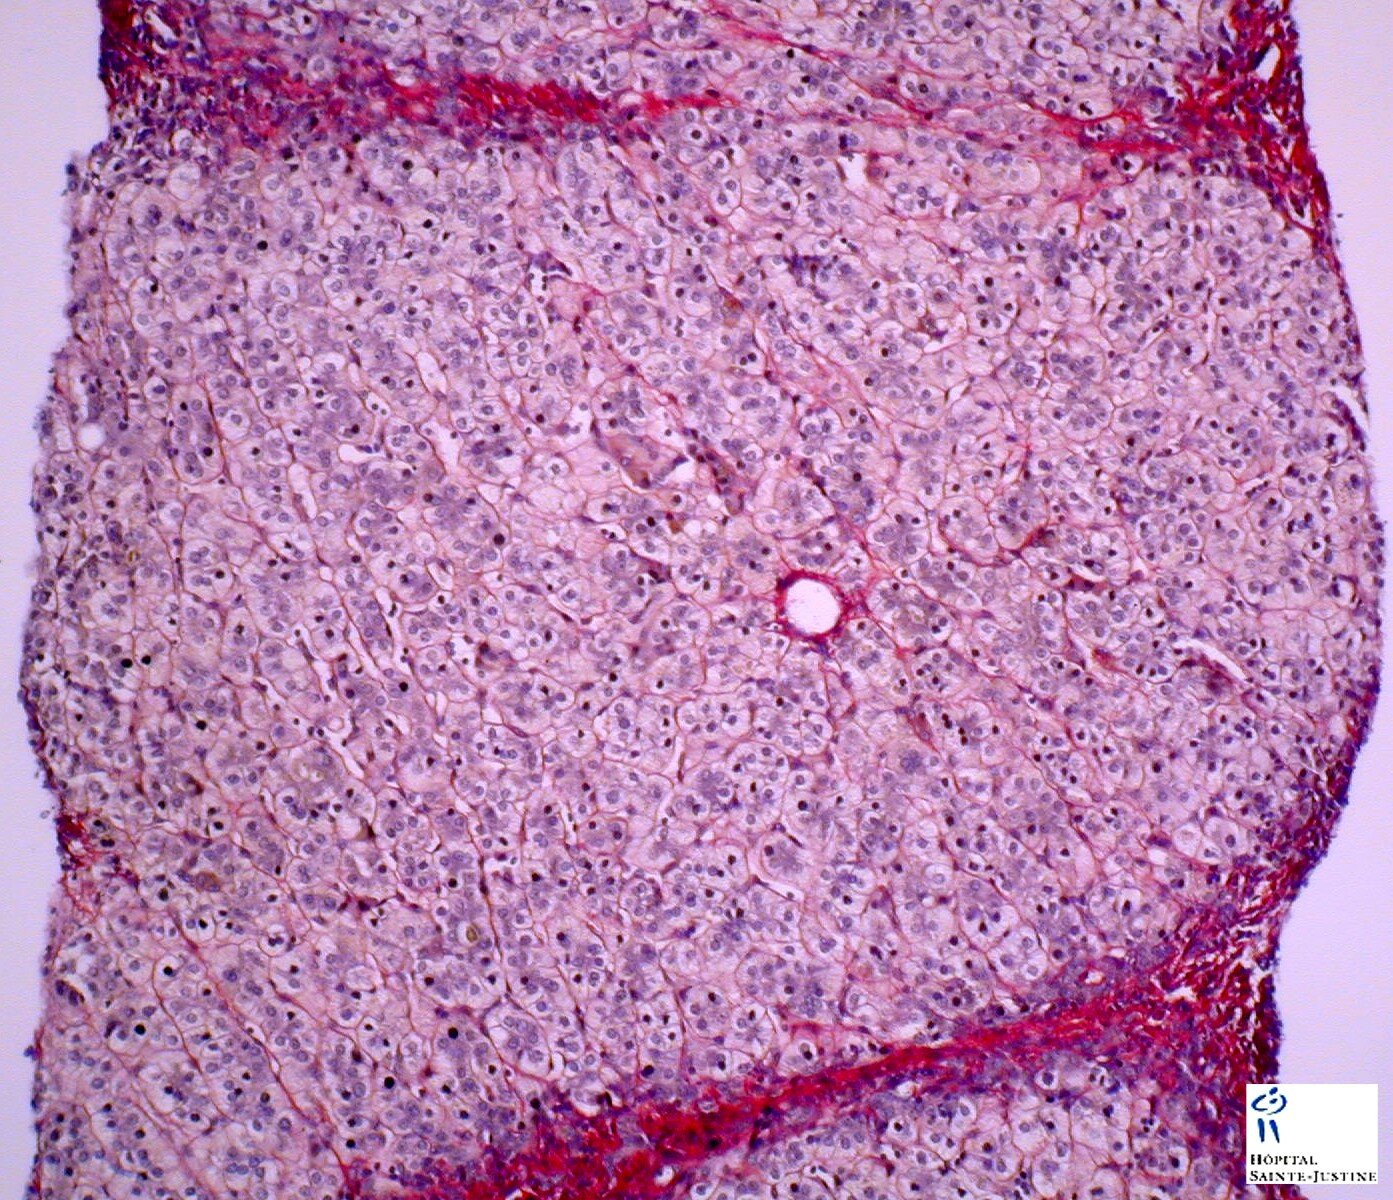

micronodular cirrhosis